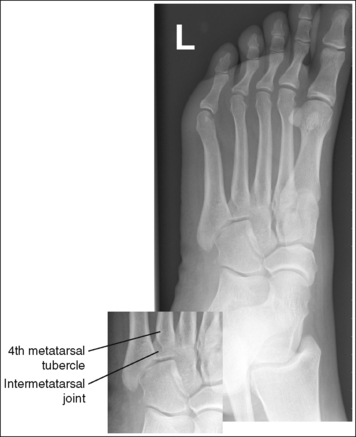

The foot demonstrates adequate obliquity. The cuboid-cuneiform joint space is open, the first and second intermetatarsal joints are closed, but the second through fifth intermetatarsal joint spaces are open, and the tarsi sinus and fifth metatarsal tuberosity are well demonstrated.

• Judging the degree of the rotation on AP oblique foot projections. On lateral foot projections, the height of the longitudinal arches can be compared by evaluating the amount of cuboid demonstrated posterior to the navicular bone. Note that more cuboid is visible posterior to the navicular bone on the lateral foot projection in Figure 6-22 than in Figure 6-20 and Figure 6-23. A lateral foot projection from a patient with an average longitudinal arch demonstrates approximately 0.5 inch (1.25 cm) of cuboid posterior to the navicular bone, whereas a patient with a high arch will demonstrate approximately 0.75 inch (2 cm) and a patient with a low arch approximately 0.25 inch (0.6 cm). On AP oblique projections, accurate obliquity has been obtained when the cuboid-cuneiform and second through fifth intermetatarsal joint spaces are open. This accuracy is demonstrated on the AP oblique projections in Figures 6-17 and 6-21, even though they were taken with different degrees of obliquity. This can be confirmed by studying the amount of first and second metatarsal base superimposition, the amount of space demonstrated between the metatarsal heads, and the demonstration of the sinus tarsi (opening between the calcaneus and talus). When the foot is rotated medially, the first metatarsal base rotates beneath the second metatarsal base, and the second through third metatarsal heads move closer together. The greater the foot obliquity, the greater the superimposition of the metatarsal heads.

• Underrotation versus overrotation. If the degree of foot obliquity is inadequate for an AP oblique foot projection, the longitudinally running foot joints (cuneiform-cuboid, navicular-cuboid, and second through fifth intermetatarsal joint spaces) are closed. To determine whether the patient's foot has been underrotated or overrotated, evaluate the intermetatarsal joint spaces between the fourth and fifth metatarsals. If this joint space is closed and the fourth metatarsal base is superimposed over the fifth metatarsal base, the foot was underrotated (see Images 15 and 16). If the fourth-fifth intermetatarsal joint space is closed and the fifth proximal metatarsal is superimposed over the fourth metatarsal tubercle, the foot was overrotated (see Image 17). The fourth metatarsal tubercle is a rounded protruding surface located just distal to the fourth metatarsal base.

The third metatarsal base is at the center of the exposure field. The phalanges, metatarsals, tarsals, calcaneus, and surrounding foot soft tissue are included within the collimated field.

• Centering a perpendicular central ray to the midline of the foot at the level of the fifth metatarsal tuberosity places the base of the proximal third metatarsal in the center of the image.

The lateral cuneiform-cuboid, navicular-cuboid, and third through fifth intermetatarsal joint spaces are closed. The fourth metatarsal tubercle is demonstrated without superimposition of the fifth metatarsal. The foot was not medially rotated enough.

Increase the degree of medial foot rotation. The amount of increase needed is half the amount of fourth and fifth metatarsal base superimposition demonstrated on the image.

The lateral cuneiform-cuboid and third through fifth intermetatarsal joint spaces are closed. The foot was not medially rotated enough.